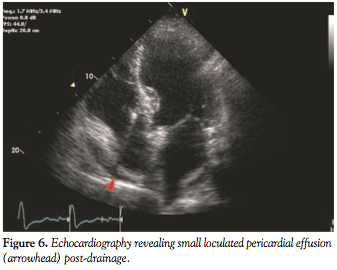

moderate supplemental oxygen, he was ultimately referred for a pericardial window by right-sided video-assisted thoracoscopic surgical approach evacuating approximately 150 ml of blood from the pericardial space and complete resolution of hypoxia. Repeat transthoracic echocardiogram demonstrated minimal pericardial fluid with no visible right to left inter-atrial shunt (Figure 6). The remainder of the patient’s clinical course was uncomplicated and the patient was discharged home on hospital day 14.